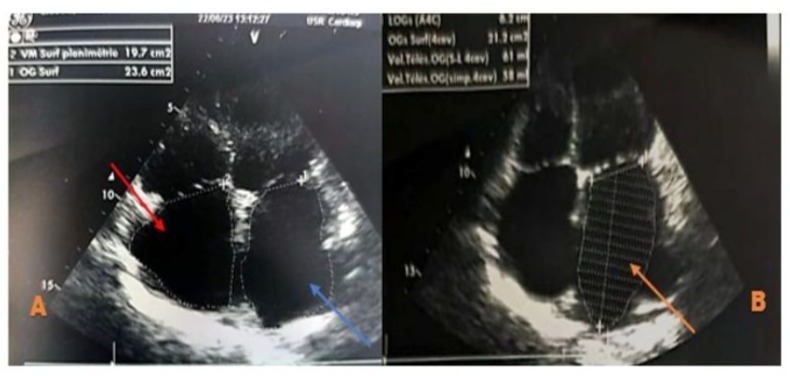

We report the case of a 70-year-old female patient with a history of poorly controlled arterial hypertension, presenting with two coexisting conditions that required either a two-step approach or simultaneous management, involving a thyroidectomy followed by cardiac surgery under cardiopulmonary bypass (CPB). In our case, a simultaneous approach was chosen following a multidisciplinary consultation. With a medical history of poorly controlled arterial hypertension, a multinodular plunging goiter in hyperthyroidism treated with carbimazole 10 mg/day, and atrial fibrillation associated to severe aortic valve stenosis managed with acenocoumarin 4 mg (¼ tablet/day) and bisoprolol 2.5 mg/day, the patient presented with a progressively worsening condition. The onset of her symptom’s dates back to five months prior, marked by a brief episode of syncope, prompting an emergency consultation. Initial evaluation revealed tachycardia due to atrial fibrillation on a background of severe aortic valve stenosis. She was placed on symptomatic treatment. The course of her illness was characterized by a worsening baseline dyspnea, progressing from NYHA class II to class III, accompanied by exertional palpitations without chest pain. The patient was referred to the ENT consultation for progressively worsening dyspnea, associated with orthopnea and a massive goiter, and cardiology consultation for the evaluation of her heart disease. During her recent assessment she also reported reduced exercise tolerance and occasional dizziness with neck symptoms, including subclavicular pain and swallowing limitations. Clinical examination revealed a large goiter deforming the neck, visible on inspection, with signs of tracheal compression. Cardiac auscultation identified an intense systolic ejection murmur at the aortic focus radiating to the carotids, with no signs of right-sided heart failure or peripheral edema. Thyroid ultrasound showed a multinodular goiter containing hypoechoic cystic areas and calcifications, with a plunging thoracic component compressing cervical and superior mediastinal structures. A cervical-thoracic CT scan, with and without contrast injection, confirmed the plunging nature of the goiter. It extended into the anterior mediastinum, displacing the trachea and major vessels without evidence of invasion. The scan revealed a multinodular goiter characterized by generalized thyroid gland enlargement, predominantly affecting the left lobe, with an irregular, lobulated contour. The goiter is characterized by heterogeneity, macrocalcifications, and uneven enhancement, marking hypodense necrotic and/or cystic fluid-filled areas. The large goiter measures 12.13 x 9.06 x 6.63 cm in the left lobe, 10.5 x 6 x 5.36 cm in the right lobe, and 5 cm in the isthmus. It extends upwards to the submandibular spaces and laterally towards the anterior and posterior spinal spaces, particularly on the left side. The jugulo-carotid vascular axes are displaced laterally and posteriorly, but remain unobstructed. The goiter extends downward into the superior level of the anterior mediastinum, filling the prevascular space and pushing vascular structures posteriorly. It reaches the level of the superior border of the aortic arch, coming into contact with the supra-aortic trunks, exerting a mass effect, but without invasion or obstruction. The upper aerodigestive pathways are unobstructed and symmetrical, although there is posterior and rightward displacement at the larynx and trachea level, without narrowing or impact on their lumen, which remains patent and of normal size. (Figure 1) Transthoracic echocardiography revealed severe degenerative aortic stenosis with high pulmonary arterial hypertension for age (PASP through tricuspid regurgitation at 55 mmHg). The left ventricle was non-dilated, hypertrophied with an indexed mass of 107.11 g/m² (eccentric remodeling), end-diastolic diameter (EDD) at 44 mm, end-systolic diameter (ESD) at 28 mm, and preserved systolic function with an ejection fraction (EF) of 55% (biplane Simpson method). (Figure 2)

Left ventricular filling pressures were normal, and the inferior vena cava was dilated to 16 mm and slightly compliant. (Figure 3,4) The left atrium was dilated, with a surface area of 21.5 cm² and a volume of 44 ml/m². (Figure 5) The right ventricle had preserved systolic function with a TAPSE (Tricuspid Annular Plane Systolic Excursion) of 22 mm and a tissue Doppler S’ velocity of 12 cm/s. The right atrium was dilated at 19.7 cm², free of echoes. Assessment of the valvular apparatus showed a tricuspid aortic valve with degenerative changes, including calcified masses between the right and left cusps, limiting valve opening. Severe stenosis was noted, with a valvular area of 0.8 cm² (indexed area of 0.58 cm²), a Vmax of 3.93 m/s, and a mean gradient of 35 mmHg. The aortic annulus measured 19 mm, and minimal regurgitation was observed. (Figure 6-9)

Figure 5: Zoomed echocardiographic image in the apical 4-chamber view focusing on the atria, showing a dilated left atrium with a surface area of 23.6 cm² (Figure A, blue arrow) and a volume of 58 ml/m² (Figure B, orange arrow). The right atrium is also dilated, measuring 19.7 cm², and appears free of echoes (Figure A, red arrow).